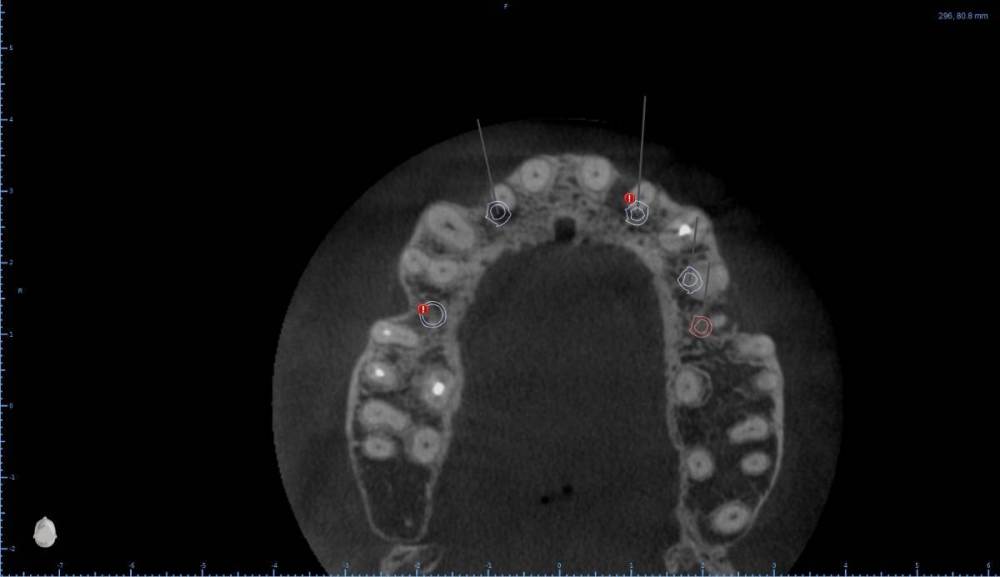

Женька Опубликовано 6 августа, 2022 Поделиться Опубликовано 6 августа, 2022 В общем планируется большая (по крайней мере для меня) работа. Вот такой товарищ у нас. Делали бы НКР в области 2.5з? или поставили бы чисто по кости, а оголённый участок закрыли присыпкой и мембраной? Также вопросы по двойкам имеются. Бугор есть, сразу оговорюсь, правда только с одной стороны. Также не понятно пока "как его правильно готовить" этот бугор, чтобы закрыть такие дефекты вестибулярной пластинки. Скрины постарался нарезать по максимуму. Там ещё будет ортодонтия конечно же. Интрузии, движения всякие и тд) Да, знаю, что планировать без цифрового гипса неправильно, но что имею. Ссылка на комментарий

Irouil Опубликовано 6 августа, 2022 Поделиться Опубликовано 6 августа, 2022 Если будет ортодонтия, то не проще ли вытянуть двойки чтобы вырастить ткани? ИДР тут нужен основательный очень, винты придётся крутить тоже очень длинные В области премоляра не вижу смысла что-то графтить, если хочется чего-то натолкать - можно стружки со сверла упаковать в дефект, но имхо не обязательно. А если сместить винт небно и чуть аннулировать, преп только пилотным и дальше конденсировать... ну Вы поняли 1 Ссылка на комментарий